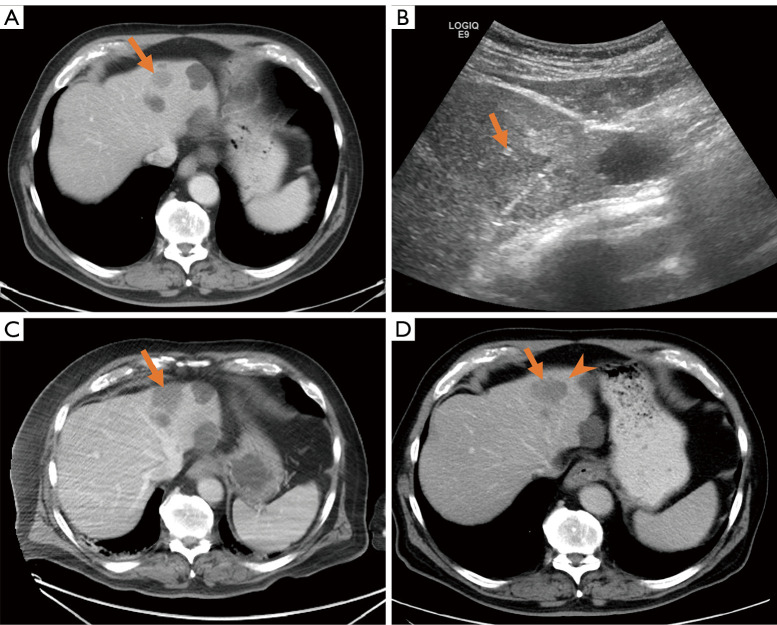

Small cell lung cancer (SCLC) is a high-grade neuroendocrine carcinoma associated with early development of distant metastases, which portends a worse prognosis. The median survival of metastatic SCLC with standard treatment is only 9-11 months, with a 5-year survival of 1-2%. Patients with SCLC are often initially responsive to systemic therapies, but once they develop resistance to them, locoregional therapies like thermal ablation should be investigated for possible improvements in morbidity and mortality. This brief retrospective report evaluates six patients with SCLC liver metastases (LMs), treated in 11 thermal ablation sessions (radiofrequency ablation or microwave ablation). Technical success was achieved in all treatments (100%). After the first ablation, 3/7 ablated tumors had residual disease. Survival outcomes were determined using the Kaplan-Meier method. Median local tumor progression-free survival (LTPFS) was 2.9 [95% confidence interval (CI): 0.5-3.9] months. Median assisted LTPFS, defined as tumor control with subsequent retreatment, was 25.9 (95% CI: 8.3-not reported) months. Median overall survival (OS) was 14.3 months. There was one adverse event (1/11) of grade 1, according to the Common Terminology Criteria for Adverse Events version 5.0, fatigue within a month of ablation, which self-resolved. The results suggest that thermal ablation is safe for SCLC LMs. Although LTPFS was very modest, the long duration of assisted LTPFS and OS in this small, retrospective study suggests that thermal ablation may be a promising treatment option.